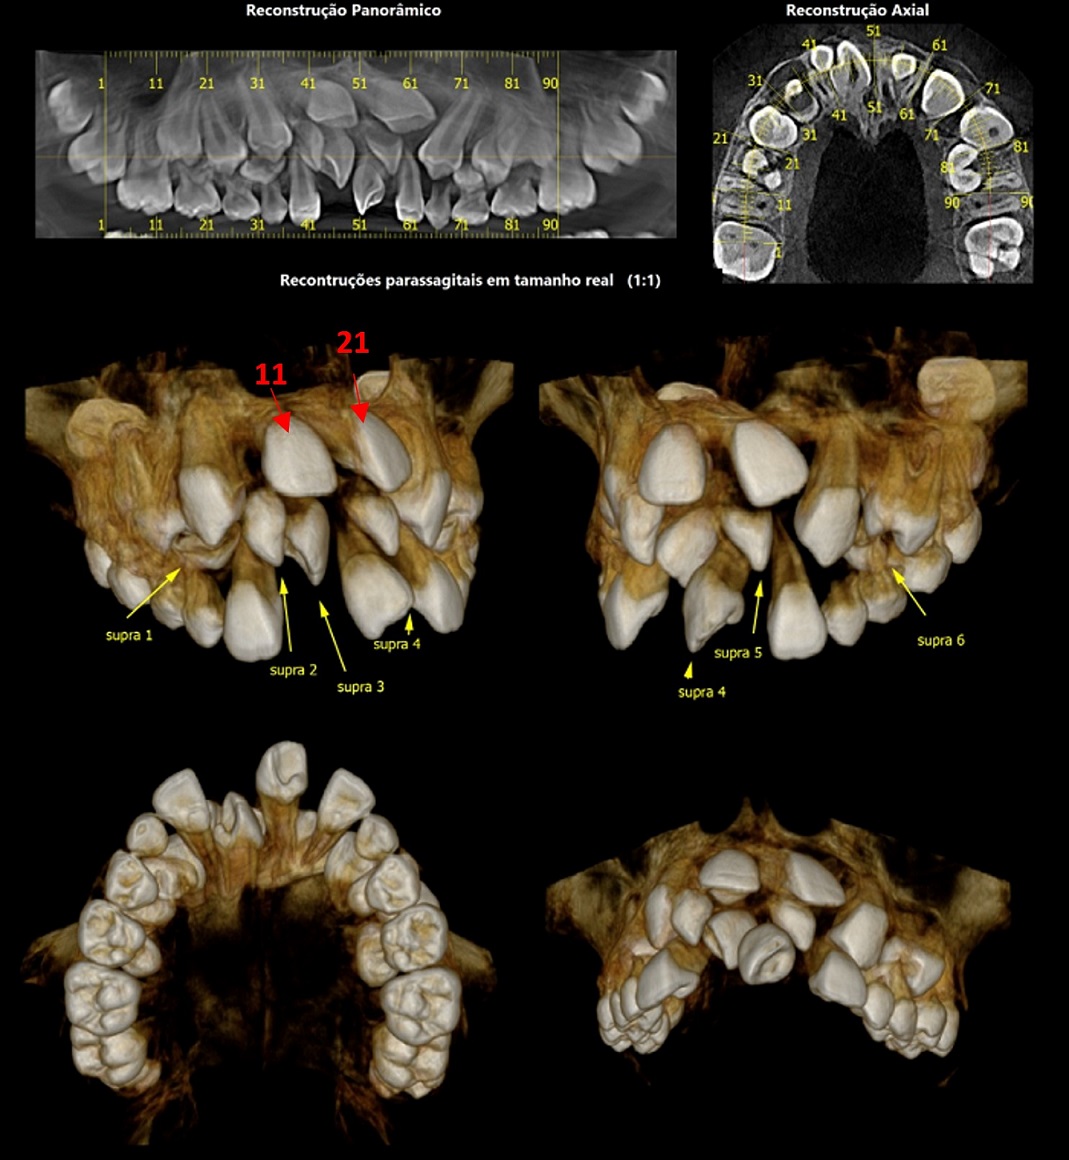

A agenesia dentária é uma anomalia relativamente comum, com prevalência na dentição permanente variando entre 2,2% a 7,6%, sendo que os incisivos laterais superiores representam 22,9% das agenesias. Considerando a posição deste dente na arcada dentária, a agenesia do incisivo lateral superior possui impacto significativo na estética, na função e no equilíbrio oclusal.

Ortodonticamente, podemos adotar 2 caminhos terapêuticos: o fechamento de espaço, por meio da mesialização dos dentes posteriores, ou a abertura de espaço, mantendo ou criando espaço para futura reabilitação protética, geralmente com implantes osseointegrados. Porém, a inserção de implantes osseointegrados requer que o paciente já tenha finalizado o crescimento ósseo. Em consequência, uma vez optado pela segunda abordagem. após o tratamento ortodôntico, precisamos preservar o espaço obtido através de próteses removíveis, próteses fixas ou, como sugerido mais recentemente, através de reabilitação com mini-implante ortodôntico e coroa estética (ROSA, 2022).